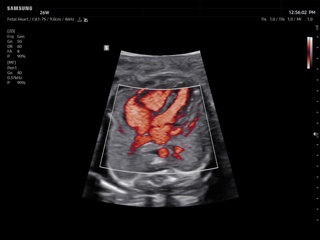

In the section "Оbsterics" of atlas the results of ultrasonic examinations of pregnant women with different durations of gestation are represented. Here you can see images of internally organs, cerebrum, cordis and the sex of the fetus, the sonograms of multiple pregnancy, the blood flow in placenta and umbilical cord, defects of fetal`s development, etc.